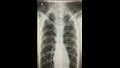

انفجرت رئة شاب، وكاد أن يفقد حياته بعد أن استنشق كمية كبيرة من غاز أكسيد النيتروز المعروف بـ"غاز الضحك" خلال حفل كان يحضره مع أصدقائه.

ونُقل الشاب الذي يدعى أليكس ليتلر ويبلغ من العمر 16 عاماً، إلى المستشفى وهو يعاني من تورم في الرقبة وضيق في التنفس وشعر بفرقعة فقاعات عند لمسه بسبب الهواء المتسرب من الرئة الممزقة، بحسب ما نقلت صحيفة "dailymail".

وذكر الأطباء أنه محظوظا كونه على قيد الحياة، ولكنهم حذروا من أنه قد يحتاج إلى عملية جراحية لإزالة الهواء المحاصر حول رئتيه وقلبه.

واكتشف الأطباء أن رئة أليكس كانت تتسرب وبدأوا في إصلاح نفسها تاركًا الهواء محاصرًا حول رئتيه وقلبه، ولحسن الحظ، نجح قناع الأكسجين الذي تم تركه طوال الليل في إزالة الهواء المحاصر دون أن يضطر أليكس إلى الخضوع لعملية جراحية.